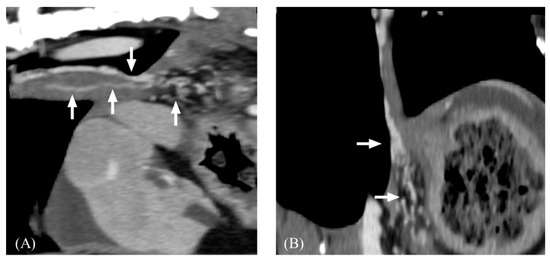

- Brancatelli, G.; Federle, M.P.; Ambrosini, R.; Lagalla, R.; Carriero, A.; Midiri, M.; Vilgrain, V. Cirrhosis: CT and MR Imaging Evaluation. Eur. J. Radiol. 2007, 61, 57–69. [Google Scholar] [CrossRef]

- Ohtomo, K.; Baron, R.L.; Dodd, G.D.; Federle, M.P.; Miller, W.J.; Campbell, W.L.; Confer, S.R.; Weber, K.M. Confluent Hepatic Fibrosis in Advanced Cirrhosis: Appearance at CT. Radiology 1993, 188, 31–35. [Google Scholar] [CrossRef]